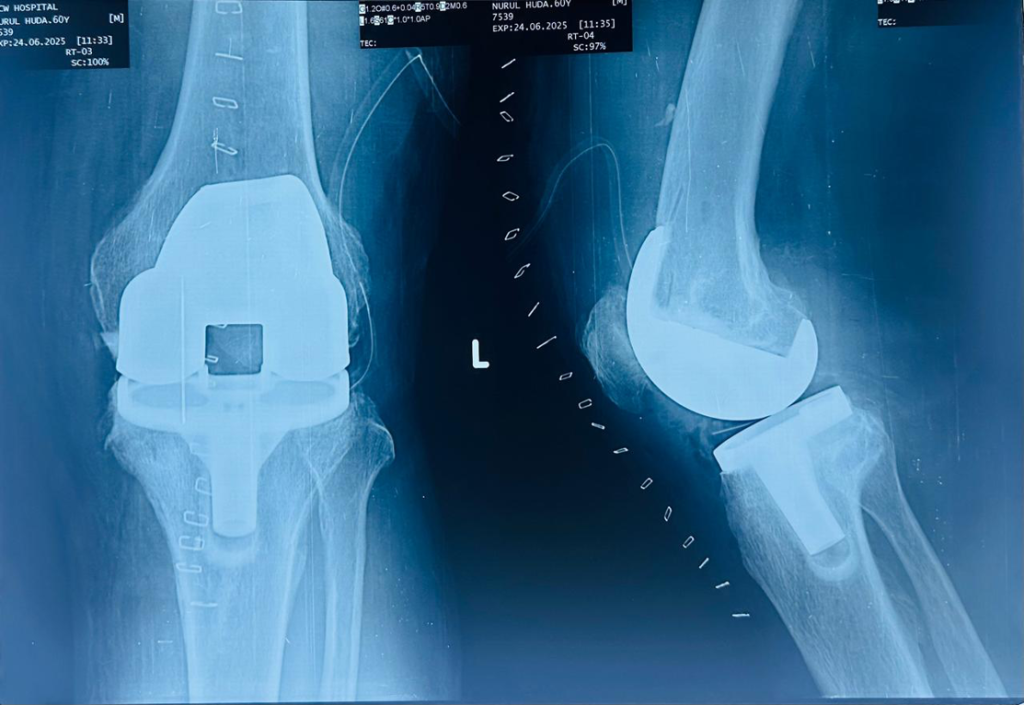

Total knee Replacement

A 60 year old male with painful, deformed both knee Before operation Total knee replacement done on left knee on 23/06/2025 Post operative x-ray: 3 days after operation